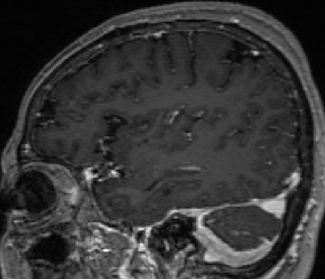

2015-4-1 MRI

2013-5-16

2013-8-2

2014-12-13

2015-4-1

2015-4-3